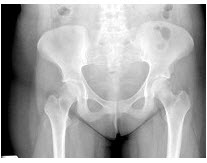

35、单项选择题

女,根据其正常骨盆影像图像,判断其最可能的年龄()